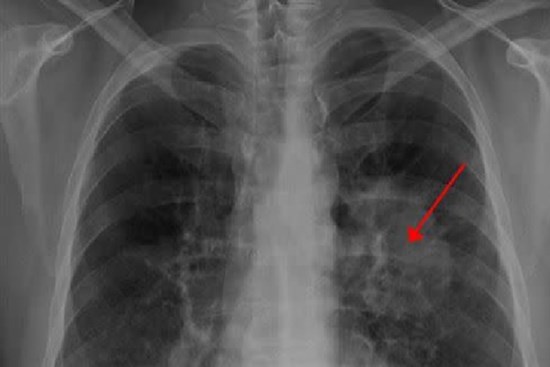

Người đàn ông ho liên tục tưởng bị cảm lạnh hóa ra bị ung thư phổi, một phần tim bị "ăn" mất, đâu là đối tượng nên đề phòng?

Ho là một triệu chứng tưởng chừng rất bình thường trong cuộc sống hàng ngày nhưng cũng có thể là dấu hiệu cảnh báo ung thư phổi đang rình rập.